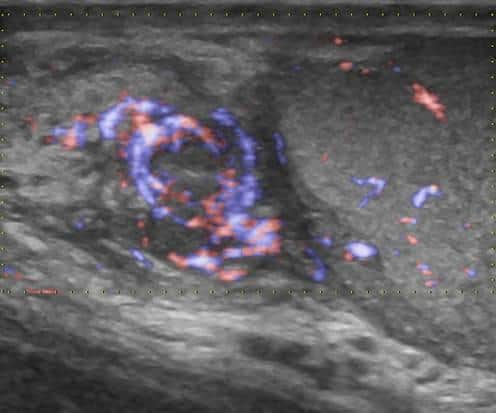

Viêm mào tinh hoàn

» Thông tin: Nam giới – 39 tuổi.

» Lâm sàng: Sưng đau vùng bìu.

# Viêm mào tinh hoàn apxe hóa.